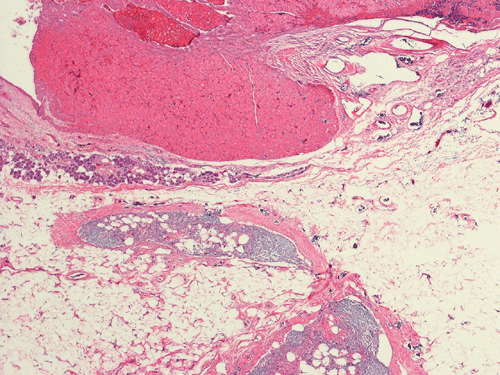

Pathology of the Case: Grossly, the tumor was a small 1 x 2 cm well demarcated nodule embedded within the mid portion of the salivary gland. There is no true capsule (Panel A). The tumor cells arrange in solid sheets and without specific pattern formation (Panel B and C). There is no collagenous tissue within the tumor. The tumor cells are polygonal and rather homogeneous in size. They have low-grade, centrally located nuclei (Panel D), finely granular and distinctly eosinophilic cytoplasm. The granular feature is best appreciated in the cytoplasmic preparation that is prepared while the tumor is being examined before fixation (Panel E). There is no necrosis or mitotic figures.

Oncocytic neoplasm of the salivary gland is recognized, as per the most recent World Health Organization (WHO) Classification 3, into two distinctive categories, namely the oncocytoma and oncocytic carcinoma. In a WHO Classification of tumor-like lesions of the salivary glands published in 1992 4, there was a separate entity of oncocytic neoplasm, nodular oncocytic hyperplasia (or oncocytosis). Nodular oncocytic hyperplasia, which was previously recognized as a distinctive oncocytic salivary gland neoplasm, represents a multifocal process, with diffuse replacement of the parotid gland with oncocytic lobules and intervening small foci of residual normal serous glands and ducts 5. Bilateral oncocytomas have been described in patient with this condition 5.

Grossly, oncocytomas are well-circumscribed, well-demarcated, round to lobulated nodules, averaging 3-4 cm in size. Oncocytomas arising from major salivary glands are usually encapsulated and those arising from minor salivary glands have less well defined borders and are usually not encapsulated. The cut surface has a typical tan-brown color. Benign oncocytomas frequently have with a central star-like scar.

Microscopically, oncocytes have a very characteristic appearance with granular eosinophilic cytoplasm due to marked increase in the number of mitochondria mitochondria, pleomorphism of mitochondria, and a paucity of other organelles. The tumor cells have little variation among different tumors or different part of the same tumor. Characteristically, the tumor cells are rather uniform and polygonal in shape. The cytoplasmic membrane can be readily recognized. The nuclei are usually round, centrally located, and nucleoli are present. The cells are arranged in uniform solid sheets without a specific pattern or they may aggregate into clusters, and sometimes they form duct-like structures. Thin fibrovascular septa are present. Oncocytomas may have a clear cell component secondary to accumulation of cytoplasmic glycogen 6. A PAS stain with and without diastase digestion will be very helpful in recognizing the glycogen. High grade nuclear atypia is only seen exceptionally. Phosphotungstic acid hematoxylin (PTAH) is a good stain that would stain the mitochondria dark. However, the stain is rarely called to service for this purpose as the cytoplasm is typically characteristic enough for recognition without special stain. In clear cell variants, however, PTAH may help. Mitotic figures are not readily seen. In most situations, the diagnosis of oncocytoma is not a particularly challenging one.